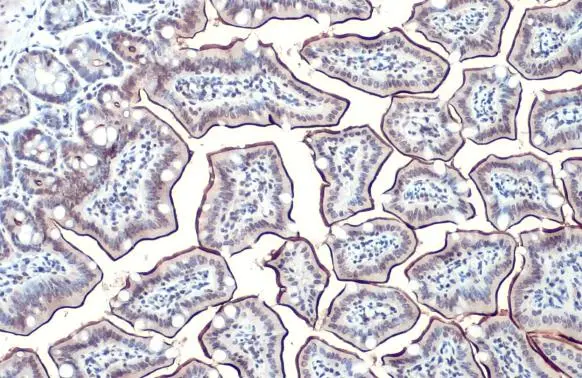

ApplicationsWestern Blot, ELISA, ImmunoHistoChemistry, ImmunoHistoChemistry Frozen, ImmunoHistoChemistry Paraffin

- Application Supplier NoteWB: 1:500-1:3000. IHC-P: 1:100-1:1000. *Optimal dilutions/concentrations should be determined by the researcher.Not tested in other applications.